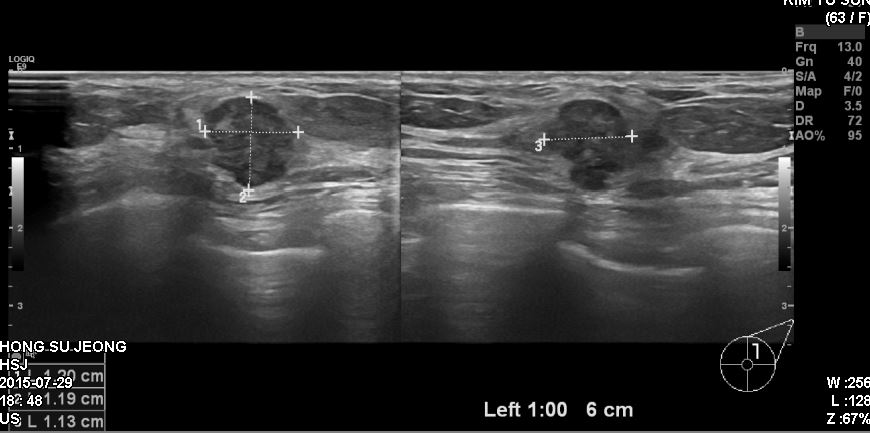

상기환자 건강검진상 이상소견으로 정밀검사 위해 내원하신 60대 여성분으로  본원에서 좌측 1시 방향에서 6cm 떨어진 곳에 의심 스러운 혹 조직검사 시행하여 좌측 침윤성 윤관암 진단되었습니다.